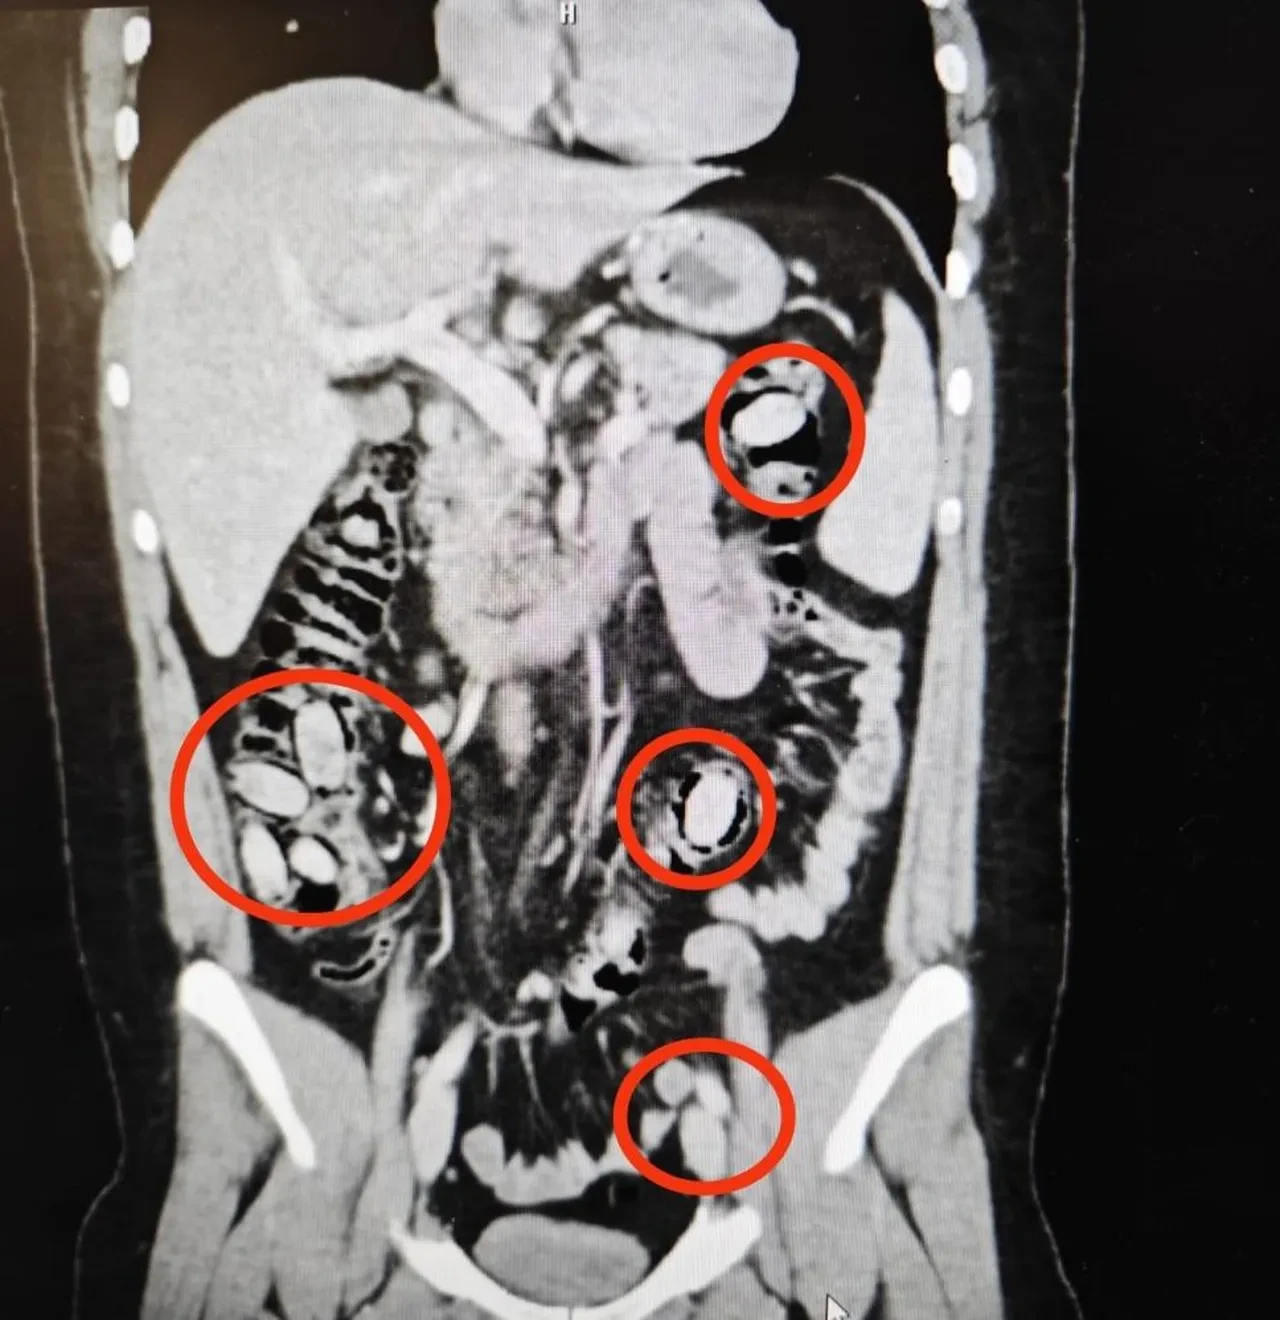

Yurtdışından Eskişehir'e gelen 25 yaşındaki S.A. isimli yabancı uyruklu şahsın kent girişindeki çevirme noktasında durumundan şüphelenilmesi üzerine hastanede yapılan detaylı tetkikler neticesinde yutmak suretiyle midesinde 44 kapsül metamfetamin maddesi taşıdığı anlaşıldı.

Cerrahi müdahaleyle söz konusu maddeler şahsın bedeninden çıkarıldı. Tedavisi akabinde şahıs tutuklandı. Yapılan titiz operasyon ile uyuşturucu maddelerin Eskişehir'de piyasaya sürülmeden ele geçirilmesi sağlandı.